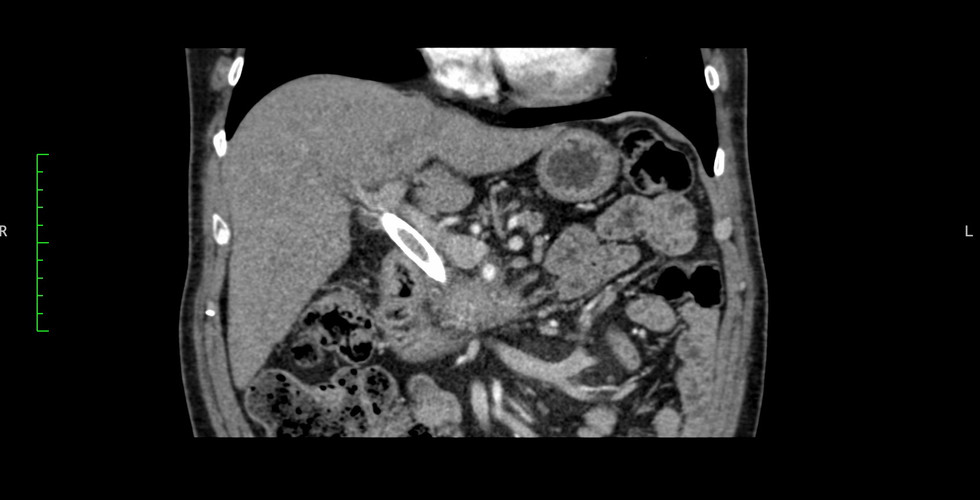

Mujer 71 años diagnosticada con cáncer de páncreas borderline (tumor de bajo potencial maligno) resecable.

Teniendo en consideración la posibilidad de que se agrave el diagnóstico, los médicos a cargo decidieron realizar una resección del tumor ubicado en la cabeza del páncreas.

La evaluación correcta del tumor era de suma importancia por su cercanía con el duodeno, la vena mesentérica superior, la vena porta hepática y la arteria mesentérica superior.

El plan quirúrgico consistió en una duodeno-pancreatectomía cefálica, que se inició con un abordaje laparoscópico y luego se convirtió en una cirugía abierta para mayor seguridad al momento de despegar el tumor de la vena porta y vena mesentérica superior.

Se utilizó modelo virtual 3D con la anatomía específica del paciente para diseñar la estrategia de resección. Esto permitió al equipo de cirujanos optimizar y disminuir los tiempos quirúrgicos: tiempo de isquemia y tiempo en quirófano, resultando en un procedimiento total de 5 horas. Además, al saber donde encontrarían los vasos que debían ligar, fueron capaces de reconocer de antemano los momentos críticos de la cirugía y disminuir el sangrado.